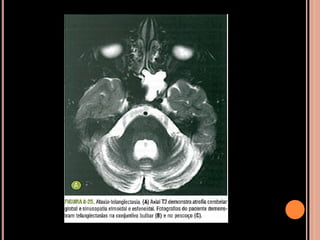

ATAXIA TELANGIECTASIA

 Ataxia cerebelar progressiva;

 Telangiectasias oculocutâneas;

 Instabilidade genômica;

 Imunodeficiência;

 Infecções sinusais e pulmonares recorrentes;

 Retardo no crescimento;

 Hipogonadismo;

 Suscetibilidade maior a neoplasias;

 1:40.000 a 1:100.000

 Telangiectasias mucocutâneas: 3 aos 6 anos de

idade; associadas à ataxia  patognomônicas de

AT;

 Vasos telangiectásicos na leptomeninge,

vascularização anormal do córtex;

 Pré-diposição a formar gliomas e

meduloblastomas;

 Timo rudimentar ou ausente;

 Aumento do CEA e redução de imunoglobulinas;